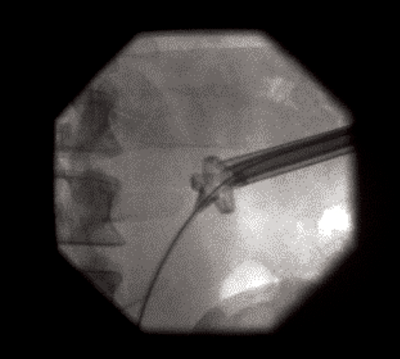

Figure 3.

The lower ureter was tortuous and of the ‘fish-hook’ type. A nephrostogram revealed a stricture at the vesicoureteric junction (VUJ) and incision of the VUJ using a Collins knife failed to demonstrate the lumen (Figure 2 and 3).